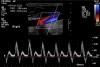

Doppler USG ürolojide en sık erektil Disfonksiyon (ereksiyon olamama, penis sertleşmesi sorunları, impotans) durumunda, nedenin araştırılmasında kullanılan bir tanı yöntemidir. Penil renkli Doppler ultrasonografi olarak yapılan Doppler USG incelemesinde; penise papaverin adlı ilaç enjekte edilir, ilacın etkisiyle ereksiyon durumuna bakılır. Penis sertleşmesinde sorun yaratabilecek, penis damarlarında tıkanıklık gibi durumlar tespit edilir. Penil renkli Doppler Ultrasonografi penise travma, darbe söz konusu olduğunda penis dokusunda zedelenme, yırtılma olup olmadığına bakılmak için de yapılır. Doppler Ultrasonografinin güncel üroloji takibinde en sık kullanıldığı durumlardan birisi de varikosel hastalığının saptanmasıdır. Bu hastalığın teşhisinde kanı toplayan damarların yapısı incelenmektedir. Penil renkli Doppler Ultrasonografi incelemesi yaklaşık 30 dakika kadar sürmektedir. -